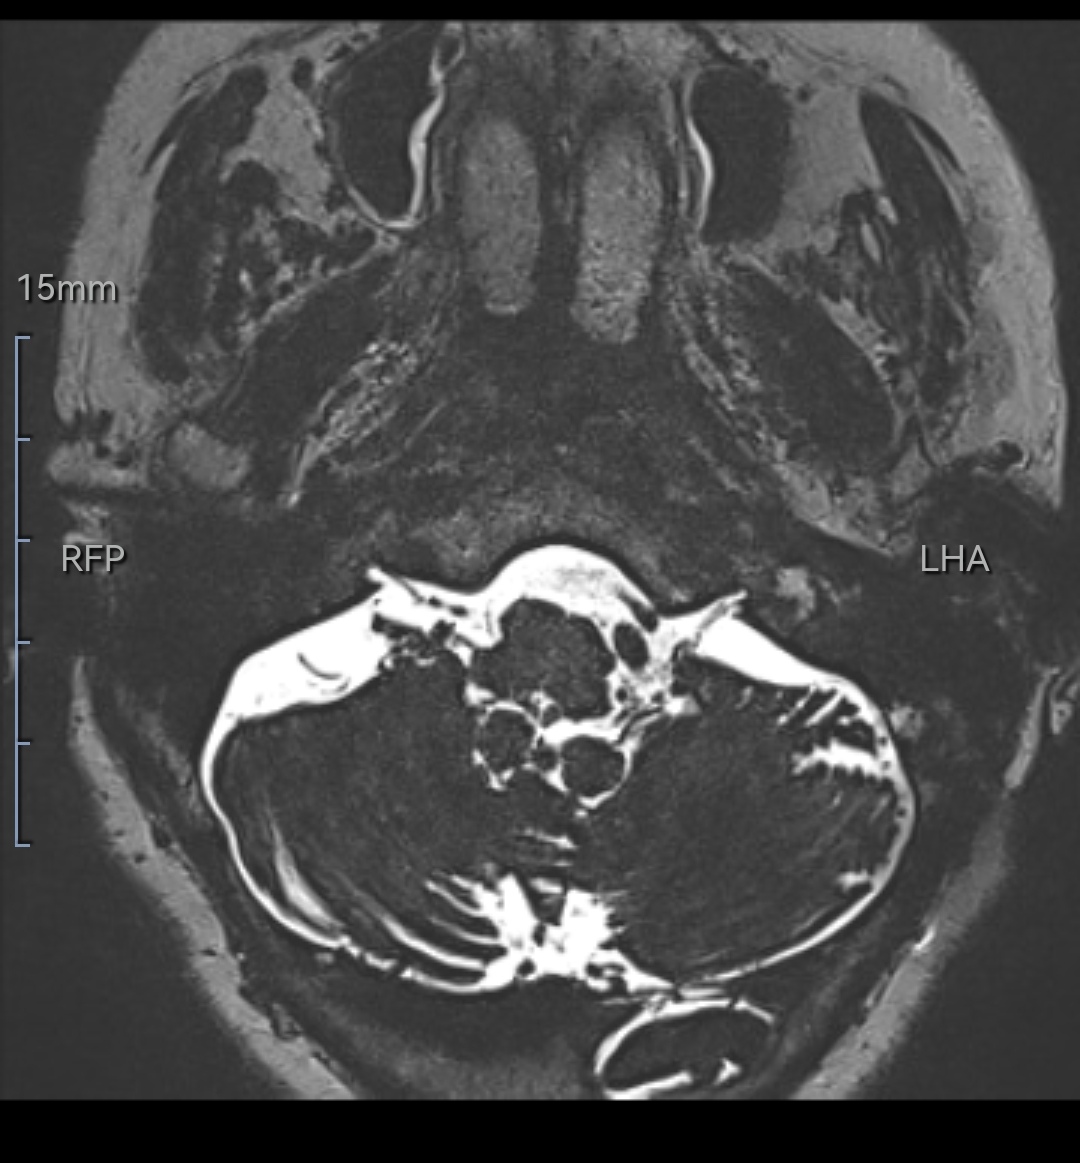

该例特点:术中见既往垫片与后组颅神经、血管粘连,硬化机化严重,剪刀、剥离子均无法撼动丝毫。

逐渐解剖,最终从后组颅神经尾端分离到操作空间,见到腹侧下方REZ区有血管卡压后组颅神经REZ区。充分松解后垫入teflon垫片,术后疼痛完全消失。

微血管减压术后复发原因可能有:早期复发与垫片漂移、垫片不到位;晚期复发可能与垫片机化粘连、其他血管卡压、蛛网膜粘连等因素有关。